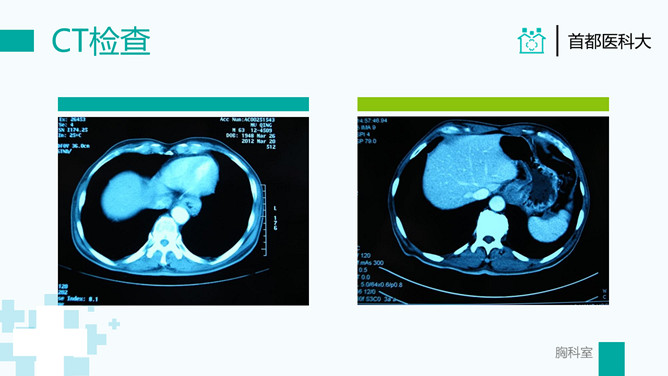

疑难病例讨论病例分析PPT模板。一套病例分析病例讨论通用幻灯片模板,简洁清新绿色主色调,医生背景。